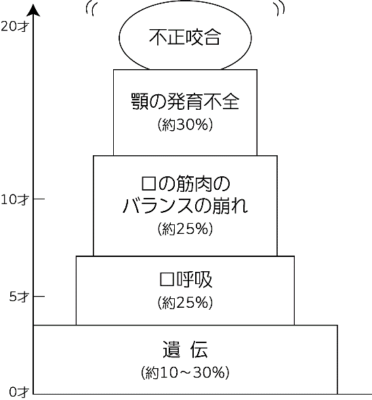

「こどもの不正咬合」は、「顎の発育不足」による症状です。

この「顎の発育に不足」は、もちろん遺伝的なもの素因もありますが、その後は、環境因子に左右されます。

環境因子→かみ合わせ・食生活・呼吸・寝方・指しゃぶり・嚥下(飲み込みかた)・咬み方・鼻づまり等です。